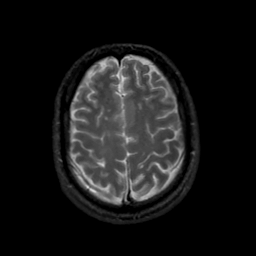

MR Study #22, December 1, 1991 -- Slice #39

[Home][Help][Clinical][Tour 1][Tour 2] Slice 39